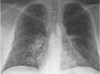

Сосудистые оперативные вмешательства сопровождаются высокой частотой послеоперационных сердечно-сосудистых осложнений. Высокий операционный риск, с одной стороны, связан с распрост.. Пневмоцистная пневмония является типичной оппортунистической инфекцией. Препаратом первой линии терапии при ней считается бактрим, альтернативными препаратами – пентамидин, клиндам..

Пневмоцистная пневмония является типичной оппортунистической инфекцией. Препаратом первой линии терапии при ней считается бактрим, альтернативными препаратами – пентамидин, клиндам.. На протяжении всей истории медицины существовало неразрывное единство афферентных и эфферентных методов лечения больных. Еще Гиппократ писал: «Медицина - есть прибавление и отнятие..